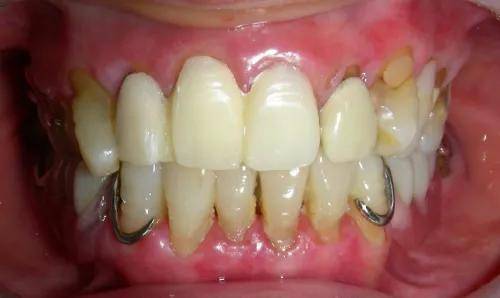

图1-2 患者治疗前和戴用临时冠的口内照片,手机拍摄,虽不理想,但足以说明问题。

于是,我取出自己的笔记本电脑,打开后调出W女士治疗前后的照片,请他们仔细看清楚。在照片上清清楚楚显示着,治疗前后的照片对比,口腔黏膜确实有些发红,不均匀的红色斑块,但是都不是很明显。治疗前后对比显示,黏膜没有任何不同。

我对他们说:“从照片上可以看出,您的治疗以前口腔黏膜和我治疗以后的黏膜情况没有任何改变,如果你们说是扁平苔藓的话,那么,也是在治疗前就存在这种情况。这绝对不是我给您做牙套造成的。”